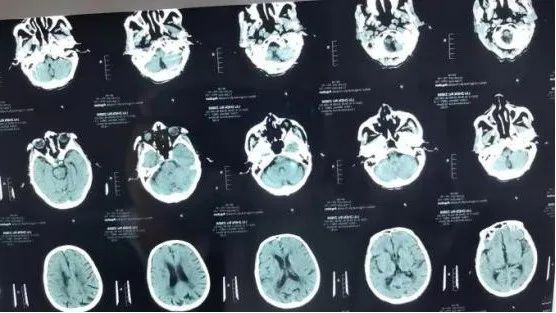

10月16日,省荣康医院内科接诊一名男性患者,86岁,突发右侧肢体无力、言语不能2小时。患者入院后,当天接诊的李梅医生立即通知来自安庆市第一人民医院神经内科驻点帮扶的王建飞医师,评估患者既往有脑梗塞、高血压病史,平素拄拐行走,现神志清楚,右侧上肢肌力0级,右侧下肢肌力2级,失语,右侧巴氏征阳性,NIHSS评分10分。初步诊断考虑为急性脑卒中,发病2小时,有可能需要进行静脉溶栓治疗。于是王建飞医师立即启动绿色通道,护士迅速完成生命体征的监测、测血糖、采血送检、完善心电图,内科储德文主任第一时间联系检验科,争取快速完成血检。王建飞医师则陪同患者前往影像科行头颅+胸部CT检查以及磁共振脑血管评估,急查头颅CT提示:1.多发腔隙性脑梗塞;2.老年性脑改变。胸部CT提示:1.肺气肿;2.两侧胸腔积液;3.心包少量积液。头颅MRA提示:双侧大脑中动脉M2段纤细。

患者高龄,起病急,症状重,有阿替普酶静脉溶栓指征,无明显禁忌症,但患者营养状况欠佳,心肺功能差,驻点帮扶的神经内科王建飞、心内科陈伟医师与储德文主任再次对患者的病情进行详细评估,充分与患者、家属沟通。考虑患者高龄、心肺功能差,一旦卧床后将出现一系列并发症,生活质量差,患者及家属商议后决定溶栓并签署知情同意书。于是,在患者入院45分钟后启动阿替普酶(rt-PA)静脉溶栓。溶栓过程中,医生和护士密切观察患者病情及生命体征变化,并持续关注患者周身皮肤及牙龈口腔黏膜有无出血点、有无头痛等不适症状。整个溶栓治疗过程顺利。溶栓后患者肢体及言语功能明显好转,溶栓24小时后复查头颅CT未见出血病灶。现患者能自行下床拄拐活动,言语流畅,右上肢近端4级,远端3级,右下肢4级,NIHSS评分3分。